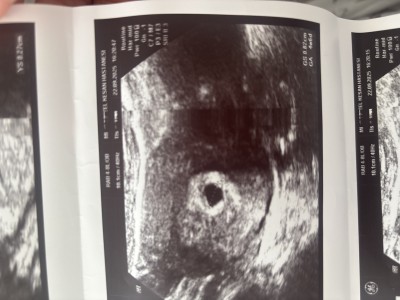

22 Eylül’de doktor randevum vardı yani pazartesi günü dün. doktor betaya göre ve haftama göre kesenin küçük olduğunu söyledi kese 0,82cm yazıyor ultrason kâğıdında. Bir önceki sorum da bu detayları vermemiştim o yüzden tekrar soruyorum lütfen bu haftalarda ya da bu beta değerinde Sizde durumlar nasıldı ya da çevrenizde böyle olup da normal gebeliğe devam eden oldu mu Fotoğrafta paylaşacağım lütfen bakar mısınız. Normalde 5 + 2 Haftalıkken ultrasonda 4 + 6 Görünüyor. Beni tedirgin eden doktorun kesenin çok ufak olduğunu söylemesi betaya göre

Gebelik haftası 5+3